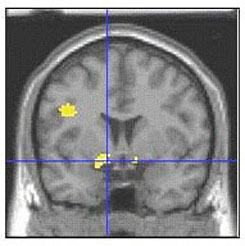

Social Phobia (Social Anxiety Disorder)

Social phobia, also called social anxiety disorder, is diagnosed when people become overwhelmingly anxious and excessively self-conscious in everyday social situations.

Social phobia affects about 15 million American adults. Women and men are equally likely to develop the disorder, which usually begins in childhood or early adolescence. There is some evidence that genetic factors are involved. Social phobia is often accompanied by other anxiety disorders or depression,and substance abuse may develop if people try to self-medicate their anxiety.